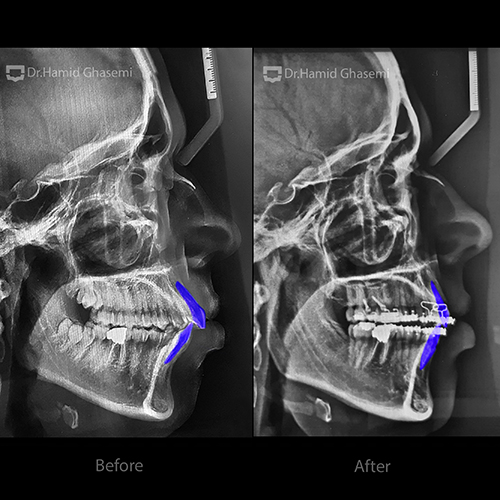

درخواست بیمار:

· اصلاح جلوزدگی بیش از حد دندانهای بالا و پایین

· اصلاح جلو بودن لبهای بالا و پایین

· عقب بودن چانه

نوع ناهنجاری:

· رابطه فکی Bimaxillary Dento-alveolar protrusion (جلوزدگی فک بالا و پایین)

· کمبود چانه به علت عدم رشد استخوان در ناحیه چانه

· زاویه بیش از حد دندانهای قدامی فک بالا و پایین به سمت جلو

طرح درمان:

در این بیمار جهت درمان جلوزدگی فک بالا و پایین، کشیدن دندانهای پرمولر اول در فک بالا و پایین و حرکت دادن دندانهای قدامی هر دو فک به سمت عقب انجام شد.

جهت جلوگیری از حرکت دندانهای خلفی به سمت جلو، دندانهای عقل نیز کشیده شدند و از اسکروهای بین ریشهای جهت کنترل بیشتر موقعیت دندانهای خلفی استفاده شد.

در پایان جراحی جنیوپلاستی چانه جهت افزایش سایز و نیز موقعیت چانه به بیمار پیشنهاد شد.

تغییرات:

· حرکت به عقب فک بالا و پایین جهت اصلاح جلوزدگی فکین

· حرکت به عقب دندانهای فک بالا و پایین جهت اصلاح جلوزدگی و زاویه بسیار شدید دندانها

· بهبود حالت لبهای بالا و پایین

· بهبود موقعیت چانه